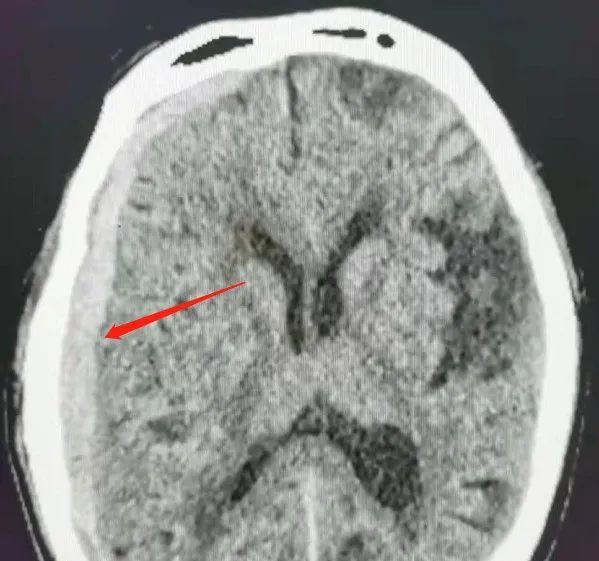

左侧硬膜下血肿并左枕叶脑出血,合并脑疝形成